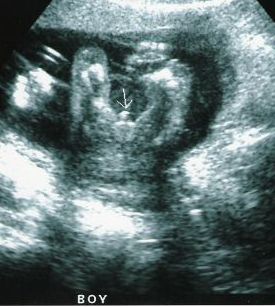

عکس جنین پسر در سونوگرافی هفته سی و سوم بارداری

آلت تناسلی پسر بطور واضح در بین پاهای او مشخص می باشد. نی نی شما در حال رشد و تکامل است و حدود 43.7 سانتی متر قد دارد و وزنش حدود 1918 گرم است.